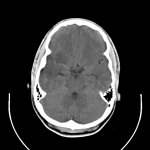

Dort angekommen wurde umgehend ein CT = (Computertomographie) gemacht.

Eine vermutete Hirnblutung konnte dadurch ausgeschlossen werden.

CT meines Schädels;

sichtbarer Schlaganfall in der rechten Hirnhälfte. |